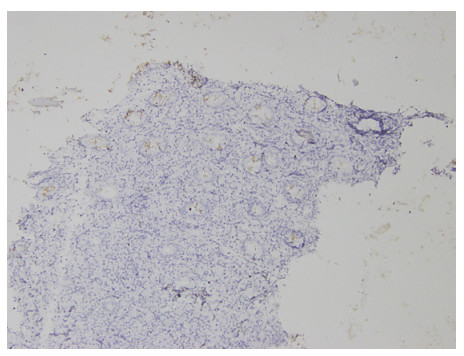

Abstract: Rectal malignancy is usually symptomatic due to its location, and most of the time presents with pain and bleeding due to its growth and ulceration. It is difficult to identify the primary as carcinoma or lymphoma based on symptoms only, as both have a similar presentation. As it presents the rarest form of histology, non-Hodgkin's lymphoma in the rectum is still difficult to diagnose initially, and its treatment is debatable. We describe the case of a 49-year-old male from Bangladesh with the same presentation. His treatment was delayed for more than a month as immunohistochemistry and staging delayed the final diagnosis. The disease was diagnosed as stage IE with the help of a positron emission tomography (PET)-CT scan, and due to the local progression the patient had a massive rectal bleeding that needed an urgent intervention. Radiotherapy was applied to stop the bleeding. Hypofraction followed by a conventional fraction of external beam radiotherapy (EBRT) with a total of 40 Gy was applied. Post-EBRT digital rectal examination showed no residual except scaring, and a PET scan was also negative for residual disease. Due to uncertainties and lack of any precious guideline, 6 cycles of adjuvant chemotherapy with the R-CHOP schedule were also completed. Without surgery, the combination of EBRT and chemotherapy helped to preserve the organ, and the patient has been disease free for more than 2.5 years since his treatment.